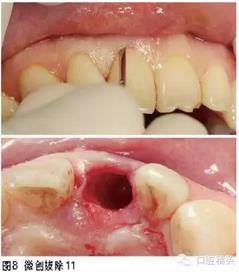

①11拔除后即刻種植即刻修復(fù)(預(yù)成臨時金屬基臺+樹脂全冠即刻修復(fù),6個月后,對11行個性化全瓷基臺+全瓷冠修復(fù));②21全瓷冠或瓷貼面修復(fù);③糾正深覆;④38、48擇期拔除。

治療過程

2.使用不翻瓣技術(shù)在拔牙窩即刻植入種植體,不僅可使水平向和垂直向的骨吸收減少,而且有利于促進相鄰位點鄰間骨高度的維持。